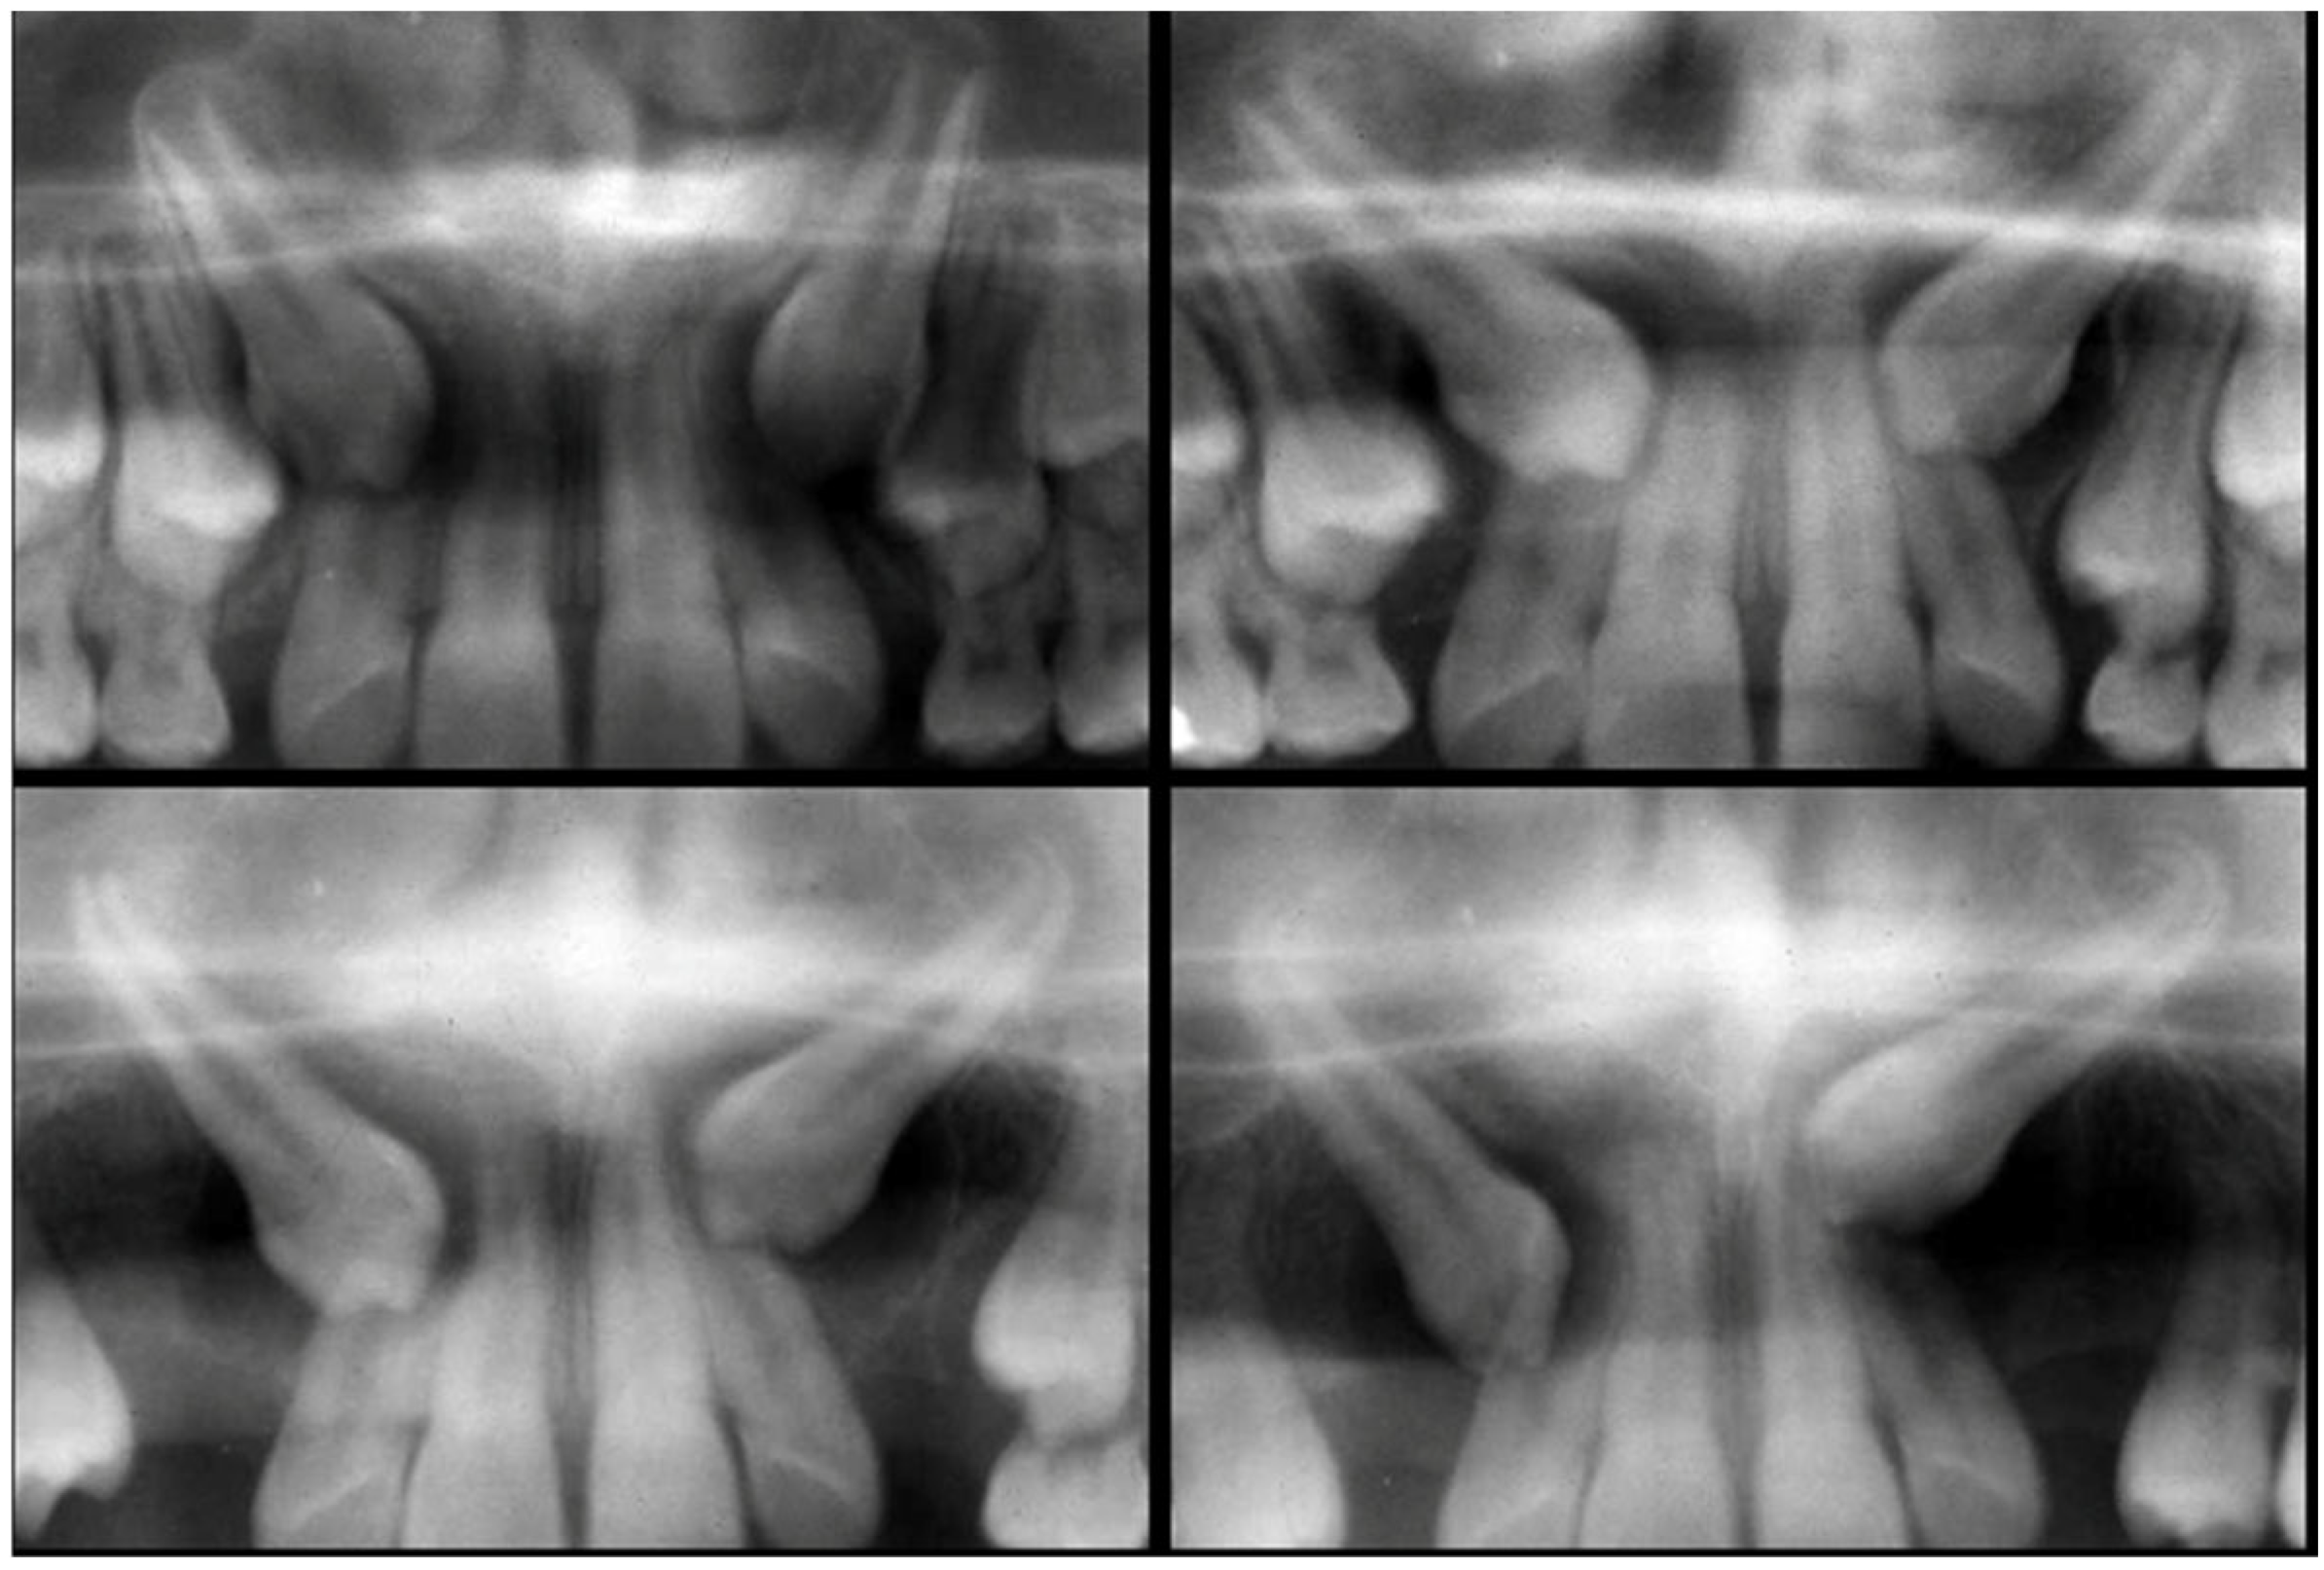

Two-Dimensional Radiographic Diagnosis of Maxillary Canine Impactions

2.2. Data Collection

2.3. Data Analysis